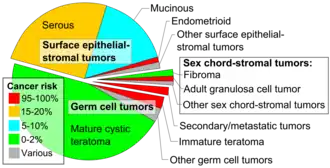

In 2020, the World Health Organization (WHO) divided ovarian tumours as 90% epithelial, 3% germ cell, and 2% sex cord-stromal types.[3]

Histopathologic classification

Tumor of the ovary vary remarkably as they may arise from any of the 3 cell types of the normal ovary.

Ovarian tumors are classified according to the histology of the tumor, obtained in a pathology report. Histology dictates many aspects of clinical treatment, management, and prognosis.

The most common forms are: